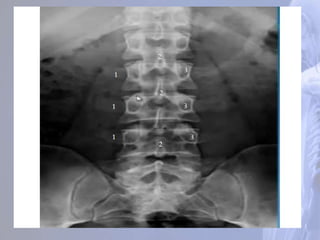

Região Lombar (LI – LV)

São as maiores e mais fortes da coluna.